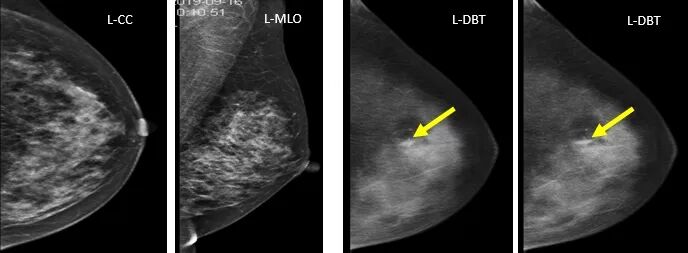

2.钙化的显示

病例4、病例5:MLO/DBT显示:肿块、形态、边缘、密度、大小、钙化显示显著优于MG,肿块边缘的分叶改变、细沙粒样征象显示更加明显。病理:乳腺浸润性导管癌。